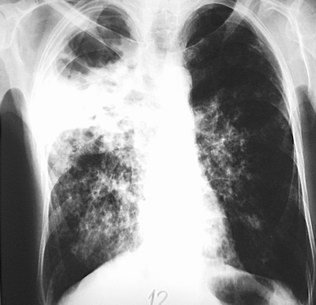

Hình ảnh lao phổi trên phim X-quang. Ảnh minh họa (nguồn: Internet). |